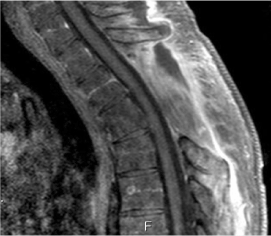

A 49 years old male patient admitted to our hospital with pain and numbness in both legs had been increasing progressively for 3 weeks after a horseshoe trauma. He had paraparesis and hypoesthesia on his neurological examination.. Magnetic Resonance Imaging (MRI) revealed a mass in 43x23 mm size with heterogeneous contrast enhancement. The lesion was in upper mediastinum, at T2 vertebra level, in left paravertebral area, extending to the spinal canal by expanding neural foramen at level T2- T3 (Figure 1). The patient was operated by neurosurgeons and thoracic surgeons together. T2 and T3 total microsurgical laminectomy, left 3rd costostransversectomy and total mass excision were applied to the patient at prone position. The postoperative neurological examination was normal. Histopathological diagnosis was “Angiomatosis”, a rare benign entitiy characterised by vascular proliferation consisting of mostly ectatic vascular structures showing multiple lobular patterns, separated by relatively good boundary from surrounding soft tissues (Figure 2).

Figure 1. In MRI; The lesion was in upper mediastinum, in left paravertebral area, extending to the spinal canal by expanding neural foramen.

Figure 2: Post operative MRI showing in operation area.